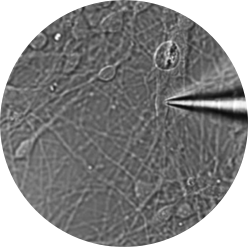

Patch Clamp recordings are performed with borosilicate electrodes of 1-2 μm tip diameter. A pipette containing an electrolyte solution is tightly sealed onto the neuronal membrane and isolates a part of the membrane (patch) electrically.

Currents fluxing through the channels in this patch flow into the pipette and can be recorded by an electrode that is connected to a highly sensitive differential amplifier. The pipette tip makes a giga-ohm seal contact with the neuronal membrane.